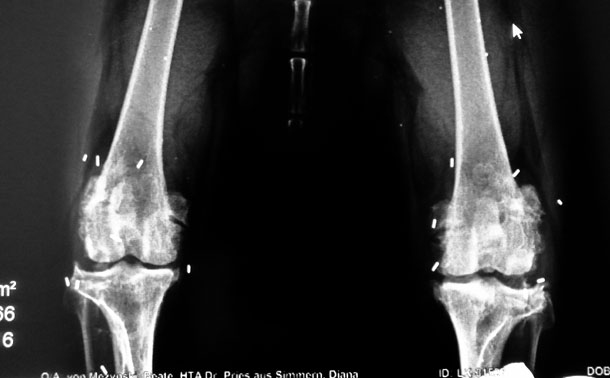

Unser Hund: Die geliebten Vierbeiner begleiten uns viele Jahre und nehmen einen wichtigen Stellenwert in unserem Leben ein. Schon nach kurzer Zeit haben wir sie ins Herz geschlossen und behandeln sie wie ein Familienmitglied. Wir sorgen für ihr Wohlergehen und kümmern uns um ihr leibliches Wohl. Deshalb trifft es einen besonders hart, wenn das geliebte Tier unter Schmerzen leidet. Eine häufige Erkrankung bei Hunden sind Gelenkbeschwerden. Ob Hüftgelenkdysplasie, Kniegelenkarthrose oder chronische Entzündungen an anderen Gelenken: Der Hund leidet unter Schmerzen und den eingeschränkten Bewegungsmöglichkeiten. Mit der Goldakupunktur kann die Tierarztpraxis Linzer in Koblenz eine dauerhafte Lösung gegen diese Schmerzen bieten.

Bei der Goldakupunktur handelt es sich um eine spezielle Methode. Dabei wird der Schmerz nicht nur kurzzeitig blockiert, sondern kann langfristig ausgeschaltet werden. Mithilfe einer Hohlnadel werden kleinste Goldstückchen an die betroffenen Gelenk-Areale geschoben. Die Wirkung des Goldes erfolgt über den stimulierten Akupunkturpunkt und die entzündungshemmende Wirkung des Goldes.